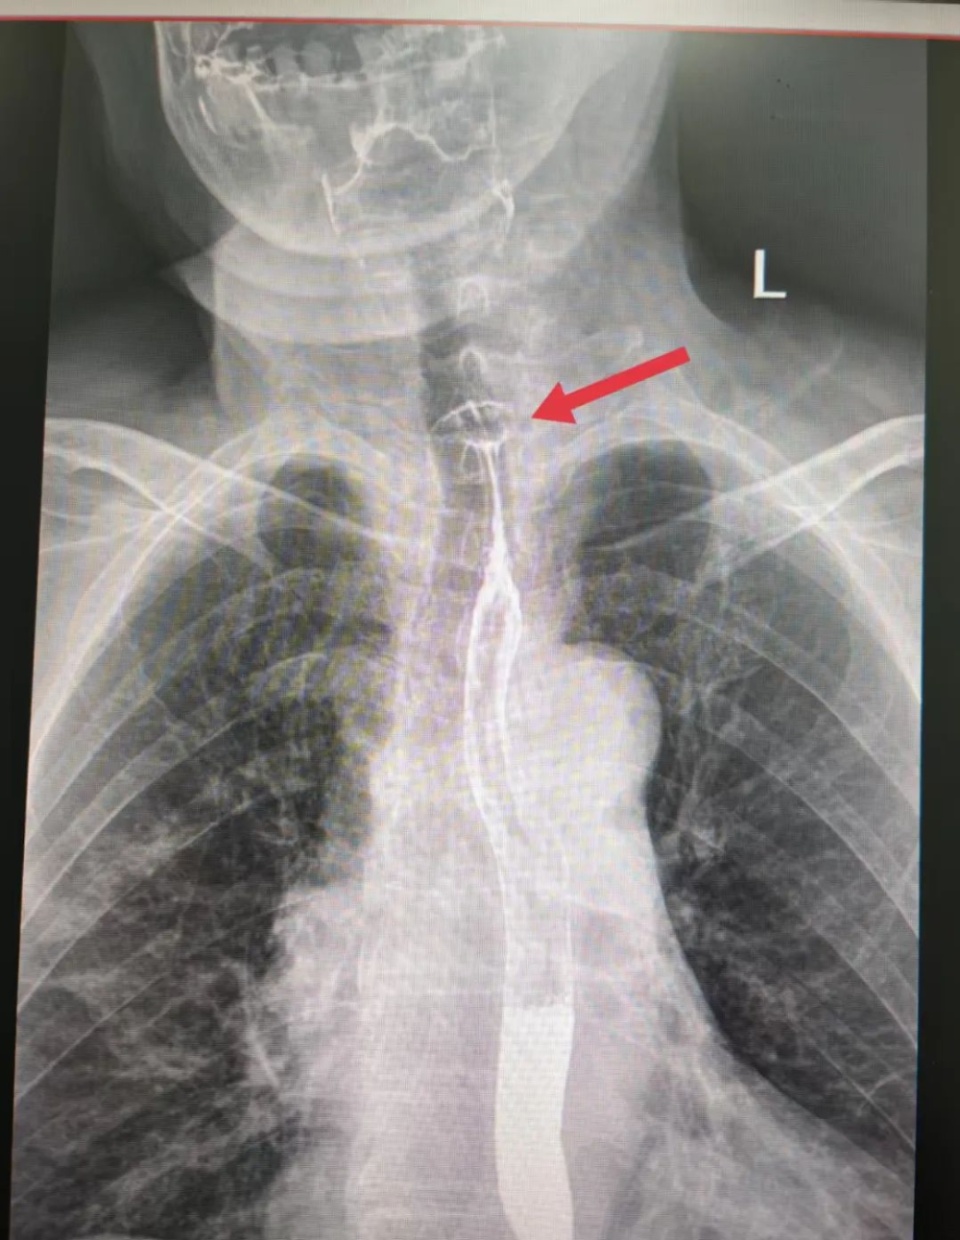

5月28日,陕西榆林75岁的高奶奶食用红枣粽时不慎吞下枣核,顿感咽喉不适、吞咽梗阻,紧急前往医院就诊。检查发现食管上段有异物,高奶奶被收治入院,经手术顺利脱险。

2.经过食管时可能卡在食管处或划伤食管,造成脓胸。因食管靠近主动脉,如果累及主动脉,可能引起大出血危及生命。